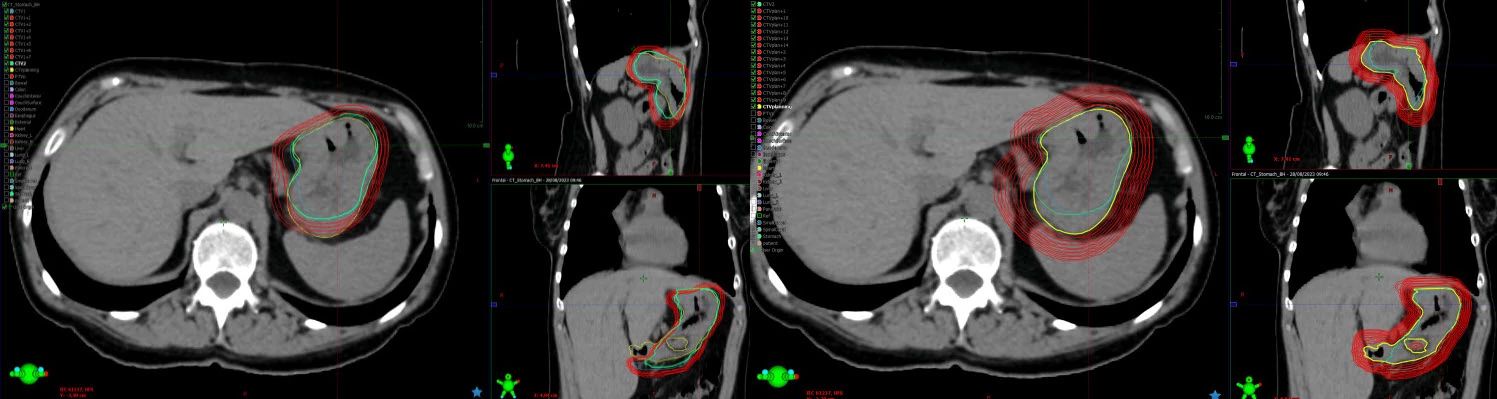

The second place case report came from Cliniques Universitaires Saint-Luc, and examined the potential benefits of oART for patients with gastric mucosa-associated lymphoid tissue (MALT) lymphoma - a rare type of slow-growing cancer that develops in the stomach's inner lining.

In this paper, researchers were able to reduce PTV margins from a standard 12mm used in non-adaptive therapy, down to just 4mm by using a breath-hold oART methodology. This resulted in significantly reduced doses to organs-at-risk and the normal tissue surrounding the target, an important goal in improving outcomes for radiotherapy patients.

Image description goes hereCBCTs from treatment session 1

CBCTs from treatment session 1 showing, in 1-mm increments, margin expansions necessary to cover CTV for adaptive treatment (left panel) and non-adaptive treatment (right panel). Margins of 4 mm were sufficient to achieve 95% coverage for the adaptive session, but for non-adaptive treatment a margin of 12 mm would be required. (From Figures 1 and 2, Tison et al.)